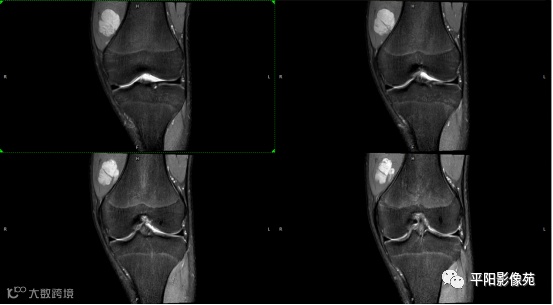

影像表现:

左膝关节股内侧肌内见多房样短T1长T2信号,内可见分隔,增强扫描明显强化,分隔未见明显强化,病灶局部与股骨远端分界不清。